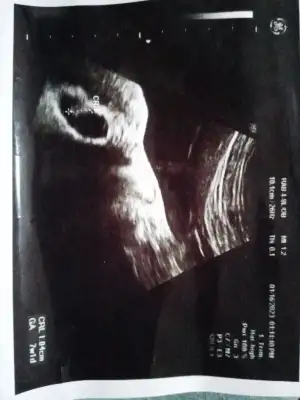

- 5 Ekim 2022

Yaş: 24

1. Çocuk

Son adet tarihi: 16.12.2022

Doğum tarihi : 22.09.2023

Şehir : Kocaeli